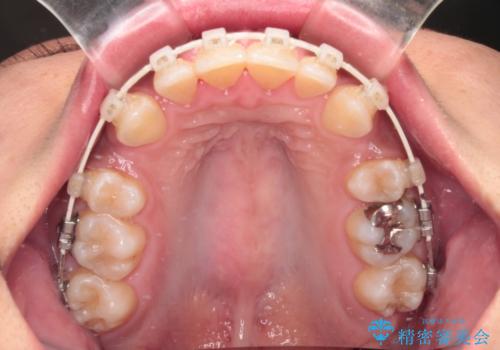

- 矯正装置

- 審美装置

- 下顎前歯部には叢生が認められ、口を自然に閉じにくい状態でした。また、噛み合わせが深い「ディープバイト」の状態で、見た目だけでなく将来的な奥歯への負担も懸念されました。

口元の突出感を改善するため、上下左右の小臼歯4本を抜歯する矯正治療を計画しました。

「矯正装置が目立つのは避けたい」というご希望があったため、プラスチックブラケット+コーティングワイヤーを使用した審美装置を選択しました。